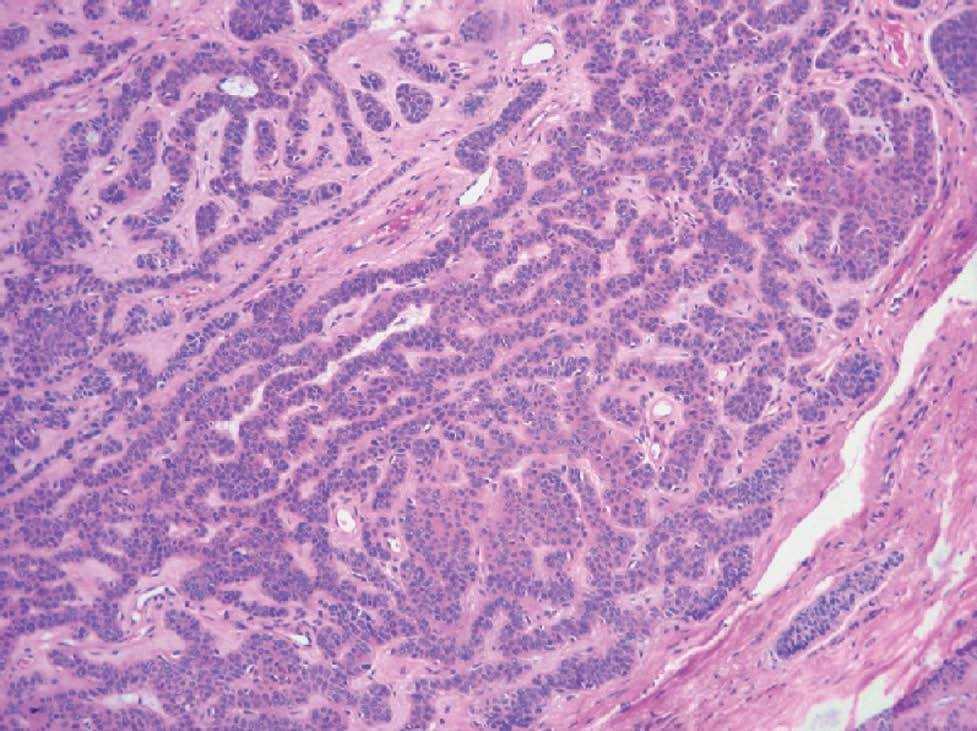

El estudio anatomopatológico revelaba una epidermis sin alteraciones destacables. Se observaba en toda la dermis y contactando con el tejido subcutáneo un tumor constituido por células germinativas foliculares que adoptaban varios patrones de crecimiento: en nódulos grandes, nódulos pequeños (fig. 2), cribiformes, racemiformes y retiformes (fig. 3). Los nódulos mostraban una parcial disposición periférica en empalizada, apreciándose en varios de ellos necrosis central y figuras de mitosis relativamente frecuentes. El estroma colágeno era denso con frecuentes fibrocitos, con zonas de aspecto mixoide, sobre todo en relación con las zonas de crecimiento retiforme, a las que también se asociaban un mayor número de quistes infundibulares. Se observaba también un componente de células claras, asociado al patrón histológico de nódulos grandes, con positividad para la tinción con ácido periódico de Schiff (fig. 4).

Fig. 3.--Patrón retiforme (hematoxilina-eosina).